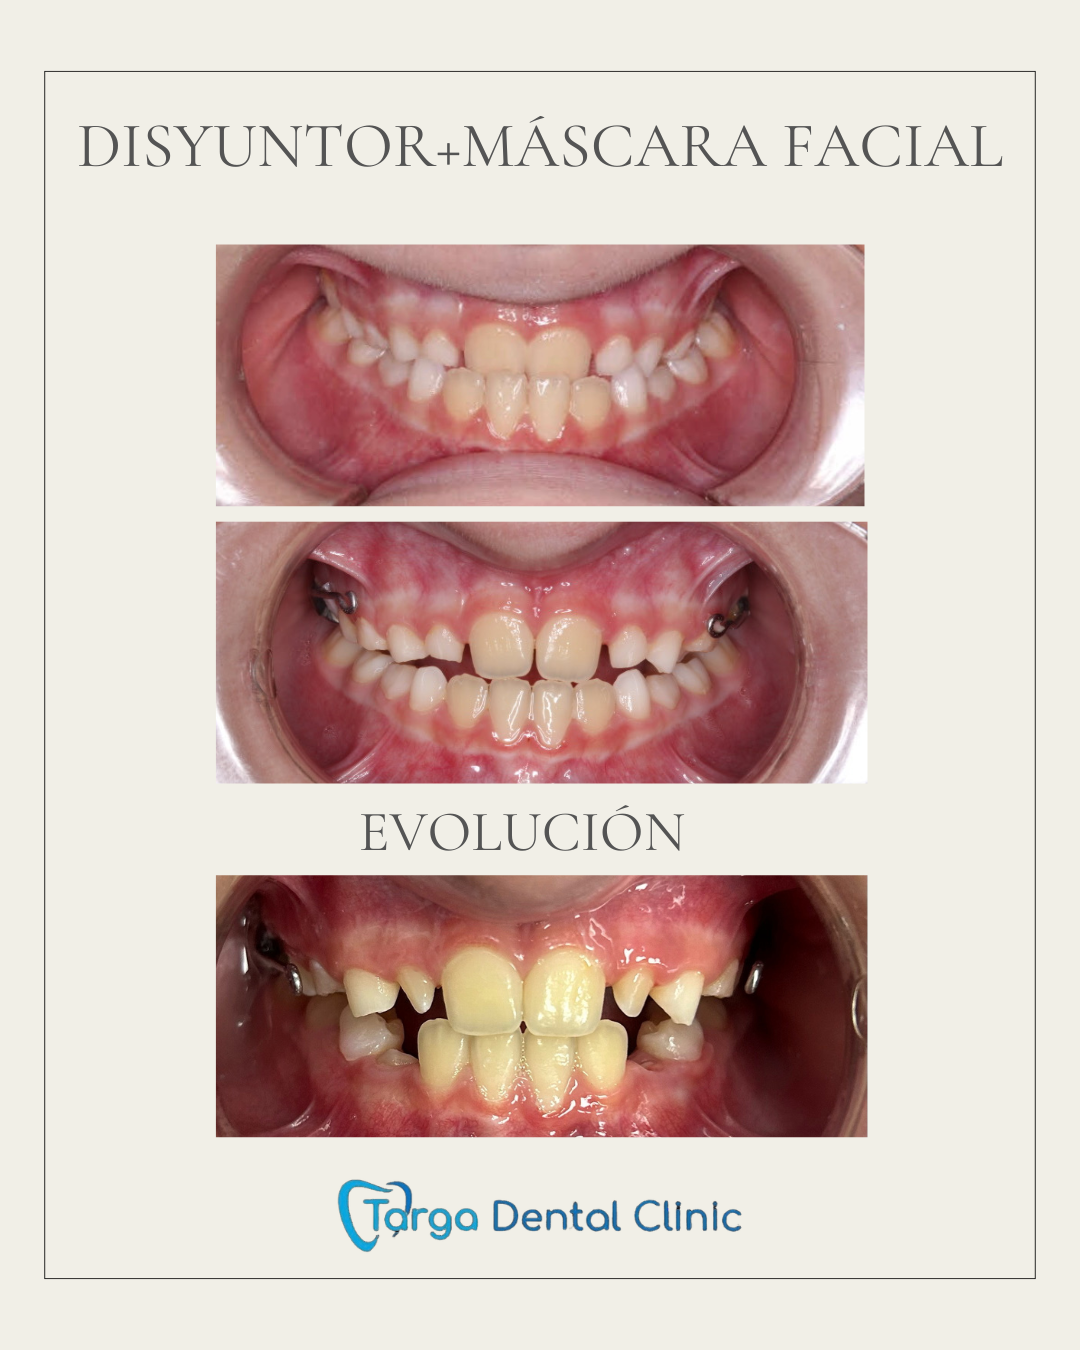

Ortodoncia y Odontopediatría

Ofrecemos tanto ortodoncia invisible con alineadores como ortodoncia fija con brackets.

Evaluamos cada caso y te recomendamos el más adecuado para ti. También ortodoncia para los más pequeños y los pacientes en crecimiento.

Tratamientos realizados en nuestra clínica